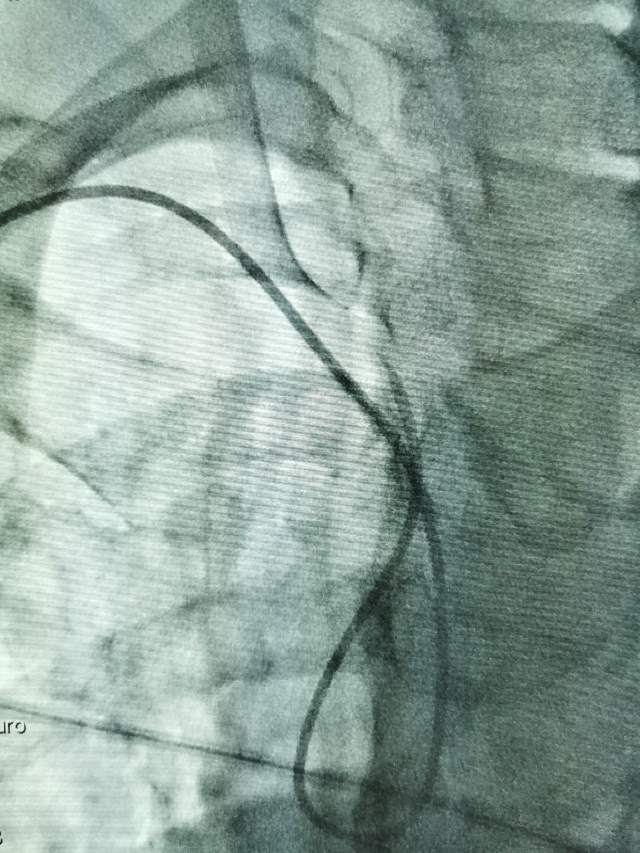

鉴于老人家体质虚弱,走路不方便,疫情期间,家人又不方便陪同,我们采用最微创的远侧桡动脉入路为老人家做了进一步检查,血管真的很扭哈,老人家也听不清楚,检查期间动来动去的,结果发现:下水道(深浅静脉系统有血栓堵塞)不通畅哦,次日给予了药物调整。治疗3天后,老人家听力明显改善,可以和医生自由交流,下床走路也如履平地,完全换了一个人哈~~~